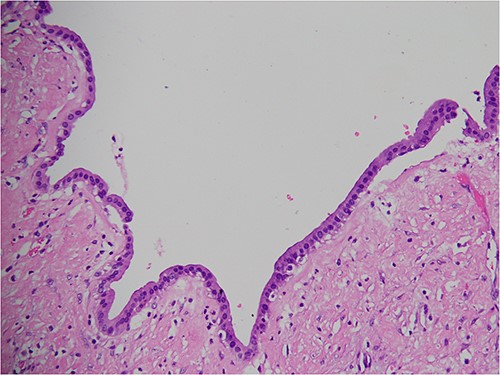

The subsequent endoscopic retrograde cholangiopancreatography showed no filling defect or luminal narrowing (Fig. 2). Pathological examination of the cyst wall revealed a benign cyst lined by cuboidal cells with acute chronic inflammation (Figs 4 and 5).

Pathological examination of the resected cyst wall showed a benign cyst lined by cuboidal cells.